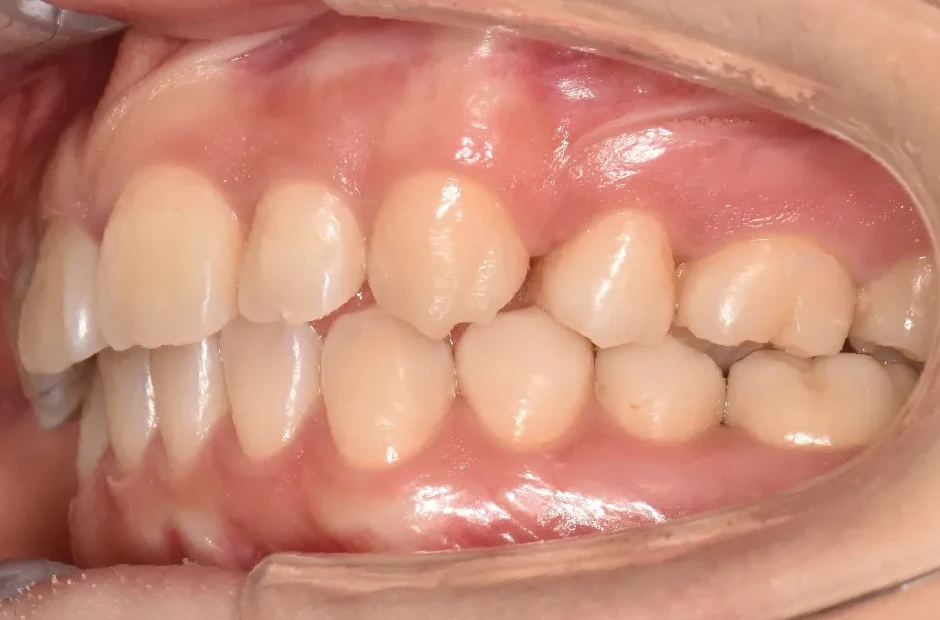

| 診断名・主訴 | ゆがみ(左右非対称) |

|---|---|

| 年齢・性別 | 20歳・女性 |

| 治療期間・回数 | 2年半 30回 |

| 治療に用いた主な装置 | 急速拡大 アンカー |

| 抜歯部位 | 左右上5番 |

| 治療費 | 70万円(税抜) |

| リスク・副作用 | 装置による違和感・疼痛・歯肉退縮・歯根吸収・虫歯のリスクなど |